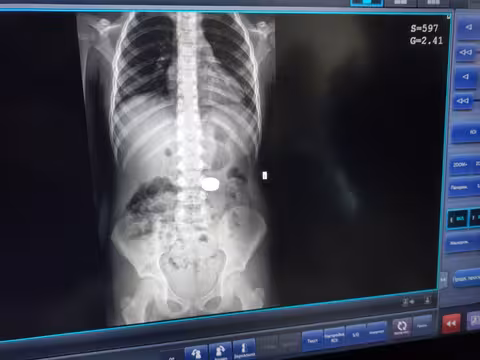

«Дівчинка сама розповіла мамі, що проковтнула магніти. Батьки звернулись у районну лікарню Миколаєва (Львівської обл). Там дитині зробили рентгенографію, і скерували у наш Центр. Ми провели додаткові обстеження, щоб визначити точне розташування стороннього тіла, та дізнатись, чи не виникли ускладнення», - розповіла гастроенетрологиня Віта Волощук

Лікар-ендоскопіст Олег Кочеркевич переконаний, що дитині певним чином пощастило: магніти були склеєні між собою й одним конгломератом впали у шлунок.

«Магніти були великого діаметру. Під їхньою вагою шлунок опустився до рівня тазових кісток. Тому спочатку візуально вони локалізувались у кишківнику. Проте ми провели пацієнтці додаткове рентгендослідження у лежачому положенні, і зрозуміли, що сторонні тіла ще у шлунку, тож можна видалити їх ендоскопічно», - додав фахівець.